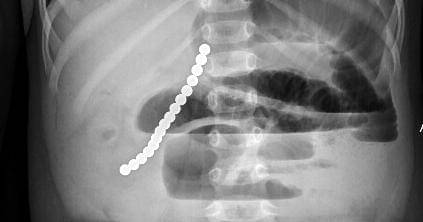

- Jika anak memiliki gejala sakit perut yang tidak dapat dijelaskan setelah kehilangan magnet, maka pertimbangkan kemungkinan bahwa anak telah menelan magnet ini. dan segeralah bawa ke ruang gawat darurat untuk evaluasi x-ray.

- Jika dokter mengatakan hanya ada satu magnet dan anak boleh pulang, pastikan Mama melakukan setidaknya dua x-ray yang berbeda. Karena dua magnet yang menjebak di antara usus dapat muncul sebagai satu magnet ketika mereka saling menyatu dalam gambar sinar-x.